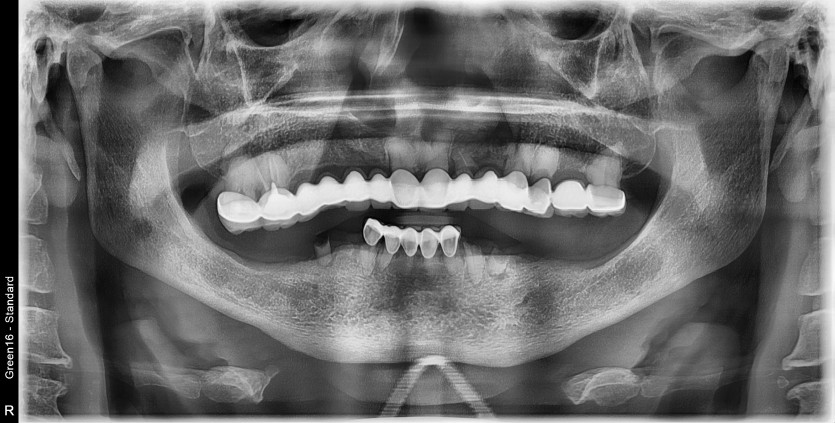

만 59세 전체 임플란트 증례

전체 임플란트 증례입니다.

16개의 임플란트로 완성하였습니다.